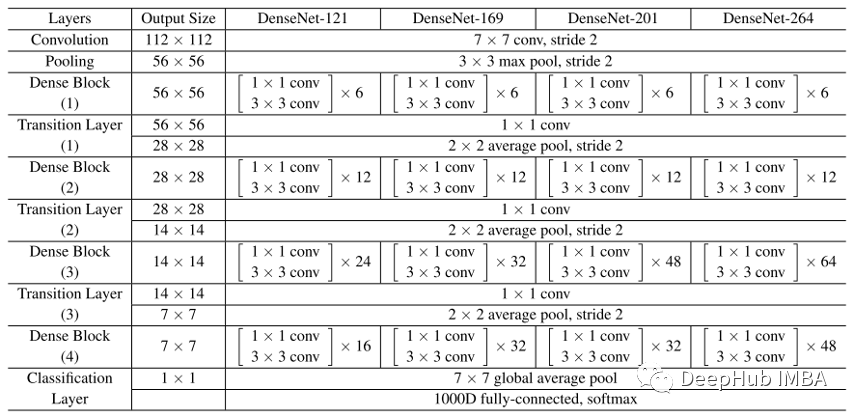

**ChexNet **

ChexNet 是一种深度学习算法,可以从胸部 X 光图像中检测和定位 14 种疾病。 在 ChestX-ray14 数据集上训练了一个 121 层的卷积神经网络,该数据集包含来自 30,805 名独特患者的 112,120 张正面视图 X 射线图像。 结果非常好超过了执业放射科医生的表现。

我们使用 ChexNet 预训练的权重来使用迁移学习获得 X 射线的嵌入。 由于 ChexNet 权重在 ChestX-ray14 数据集上的疾病分类等任务中得到了很好的收敛。

论文:https://arxiv.org/pdf/1711.05225v3.pdf

权重文件:https://www.kaggle.com/datasets/theewok/chexnet-keras-weights

ChexNet 使用与主干类似的架构是 DenseNet121,下面是 DenseNet 架构。